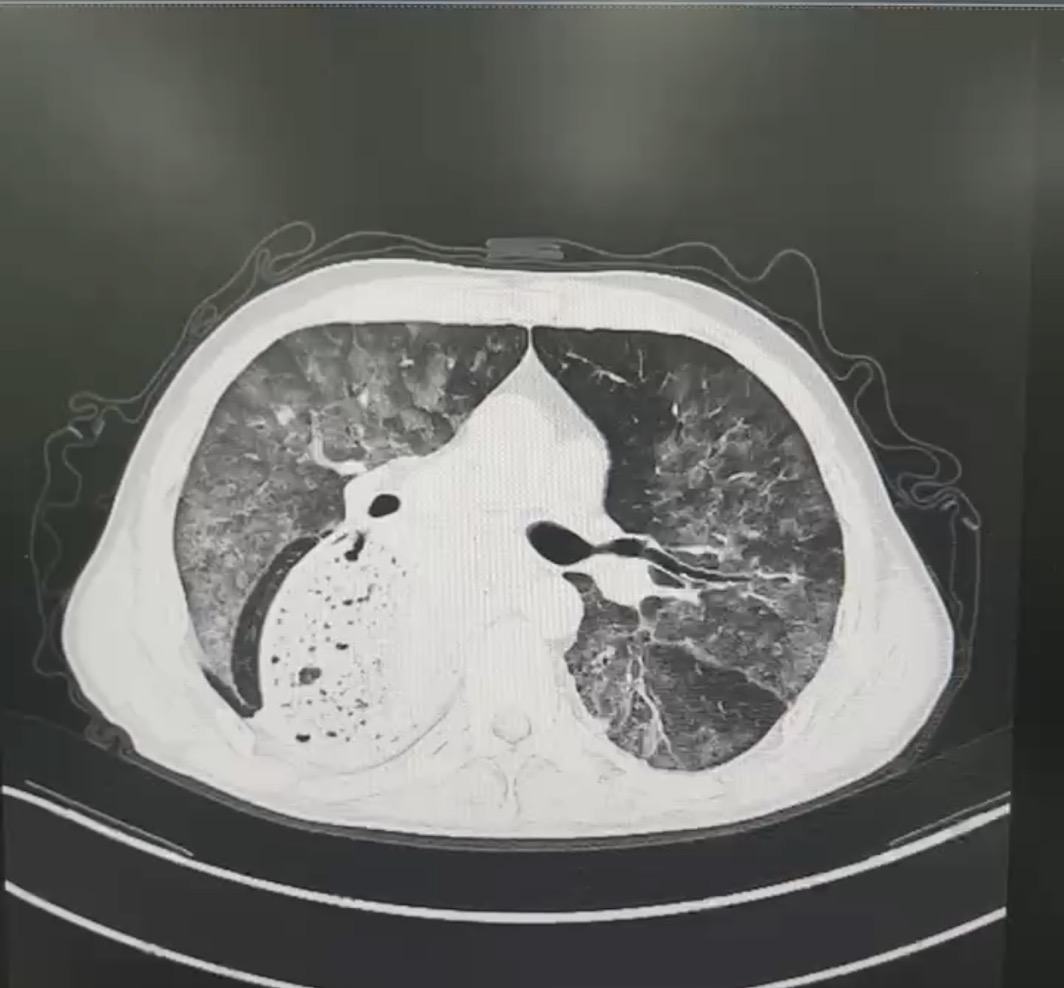

入院后,医生迅速展开全面细致的检查,支气管镜检查发现患者肺泡灌洗液成米汤样,并具有明显分层现象,结合后续肺泡灌洗液报告,中性粒细胞占比高达99.0%,并可见吞噬细胞,镜下可见大量脂肪空泡,苏丹 III 染色呈阳性,这些证据指向疾病的最终真相——脂质性肺炎。

肺泡灌洗液分层